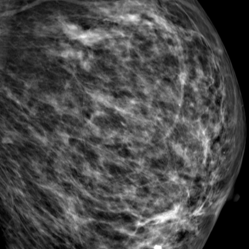

Refer to caption

Figure 4: Segmentation masks of OCT data, where fθf_{\theta}^{\star}italic_f start_POSTSUBSCRIPT italic_θ end_POSTSUBSCRIPT start_POSTSUPERSCRIPT ⋆ end_POSTSUPERSCRIPT outperforms fθf_{\theta}italic_f start_POSTSUBSCRIPT italic_θ end_POSTSUBSCRIPT.

Figure 5: Segmentation masks of Dermoscopy data, where fθf_{\theta}italic_f start_POSTSUBSCRIPT italic_θ end_POSTSUBSCRIPT outperforms fθf_{\theta}^{\star}italic_f start_POSTSUBSCRIPT italic_θ end_POSTSUBSCRIPT start_POSTSUPERSCRIPT ⋆ end_POSTSUPERSCRIPT.

The results show that edge-enhanced pre-training yields significant performance improvements in certain imaging modalities while degrading segmentation quality in others. Exemplary cases, where both fθf_{\theta}^{\star}italic_f start_POSTSUBSCRIPT italic_θ end_POSTSUBSCRIPT start_POSTSUPERSCRIPT ⋆ end_POSTSUPERSCRIPT and fθf_{\theta}italic_f start_POSTSUBSCRIPT italic_θ end_POSTSUBSCRIPT significantly outperform each other can be seen in fig.˜4 and fig.˜5. This variability highlights the importance of aligning preprocessing strategies with the inherent characteristics of each modality rather than applying a uniform approach. Through the analysis of statistical meta-features—standard deviation and image entropy—, we identified indicators for anticipating when edge emphasis would be advantageous. Leveraging these indicators, we developed a selection mechanism that outperforms generic pre-training strategies, optimizing segmentation accuracy. While we focussed on the meta-features standard deviation and entropy due to the closeness to pixel intensities, which are determined by the use of edge operators, we encourage further work on higher-dimensional methods for meta-classification like a shallow convolutional neural network or an image encoder. Given that no universally optimal edge filter exists for all images [13], achieving consistent cross-modality improvements in segmentation quality presents a considerable challenge. With the specific edge kernel used in data pre-processing for foundation models vastly determining performance gains and losses, different edge kernels like Sobel [6] or Prewitt [16] should be examined to identify influences in performance. Since applying edge enhancement in pre-training of foundation models exhibiting great performance increase, we suggest further research on the application of edge enhancement in the subsequent fine-tuning of foundation models. Integrating multiple filters within a unified model selection framework could also improve adaptability. Alignment between certain edge filters and certain imaging modalities pose vast potential for futher increase in segmentation performance. Moreover, applying edge enhancement not only at the pre-training stage but also during subsequent refinements remains an avenue for future work. While we validated the benefits and restrictions of using edge-enhanced data in pre-training of foundation models, we recommend further work on increasing computation efficiency due to increased training needs for two foundation models. In this paper, we propose applying edge enhancement on image data in pre-training of foundation models for improved cross-modality segmentation quality. By leveraging meta-features such as standard deviation and image entropy, we develop a meta-classification strategy to selectively apply edge-enhanced pre-training, achieving an cross-modality segmentation performance improvement by 16.42% compared to models pre-trained on edge-enhanced data only and 19.30% compared to models pre-trained on raw data only. For the modalities Fundus, Mammography, US, and XRay, vast performance gains can be achieved using our meta-classification strategy, while for OCT we recommend solely using edge-enhanced data in pre-training. Our work provides a principled framework for optimizing segmentation performance by aligning pre-training strategies with the intrinsic properties of medical imaging modalities, offering a significant step forward in the development of robust, generalizable foundation models for medical image analysis.